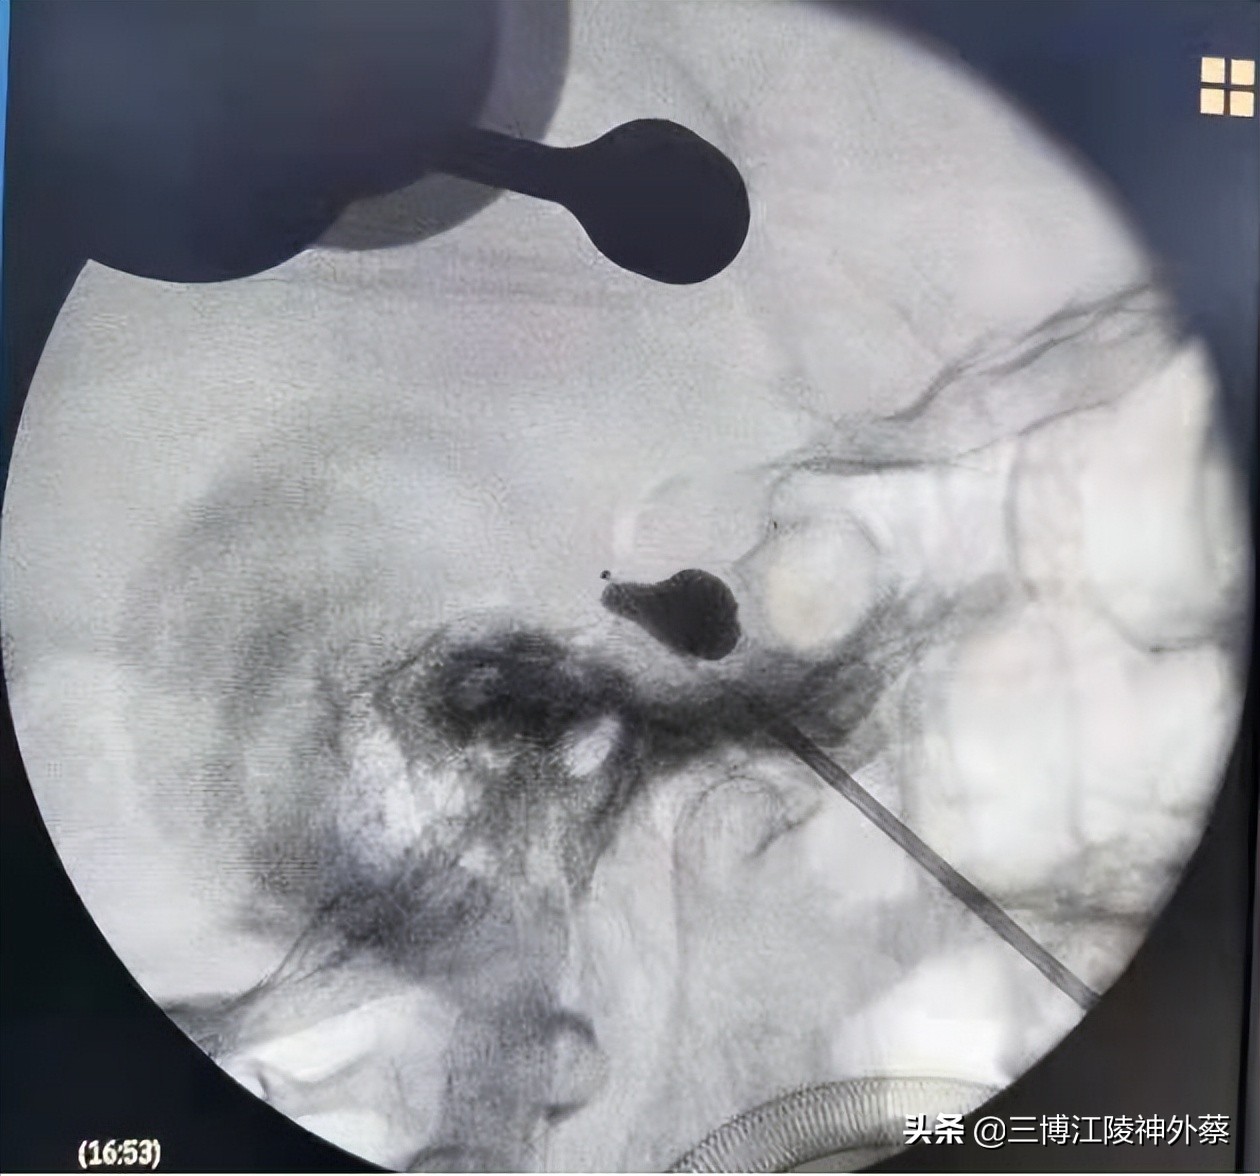

术中球囊充盈呈现完美的“梨形”

在与患者及家属充分沟通后,于2月24日在全麻下行机器人引导下左侧经皮穿刺三叉神经半月节球囊压迫术,值得一提的是,此次手术采用机器人引导,增加了手术穿刺的准确率。术后患者左侧面部原有疼痛消失,感左面部轻度麻木。